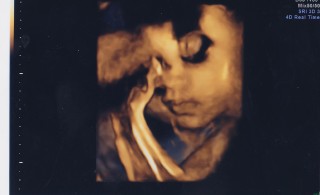

32w5d 頭77㎜お腹280㎜大腿骨58㎜体重1940g。 すくすく育ってます(*^^*) 今回はぺろっと舌を見せてくれました!指もよく動かして元気そうな姿が見られて嬉しいです。今回のエコーで性別がわかったような!?(主人は確信しているので敢えて先生には聞いてません)張りもおさまり赤ちゃんが元気なら退院できると信じて3週間経ちました、34週が節目のようです、あともう少し(^^;)もう少し頑張ろうね。

「ねんね」のポーズで、自分の腕を枕に目をつぶって寝ています。

口元がはっきり映っているので気に入っています。

ほっぺたがぷっくり出てて、目鼻立ちは夫そっくり!髪の毛も生え始めてました。

3Dエコーでとってもらいました。

天使みたいな寝顔!(はい。すでに親バカです)